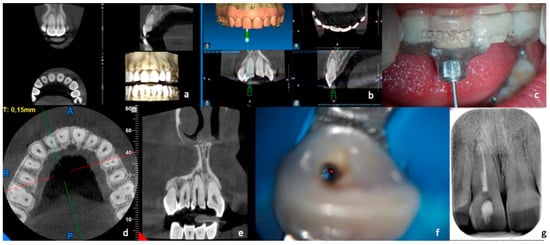

Figure 1. Treatment with “optimal precision” of a calcified canal. After carrying out a small FOV CBCT (a), which highlights the calcification of the canal, the DICOM data of the CBCT are coupled with the STL data derived from the digital impression (b). The result is a digital project that enables creation of a guide (c) which allows insertion of the two drills with a diameter of 0.9 mm up to the desired depth to reach the canal (d). The guide is inserted (e) and proceeds, with short excursion movements, to reach the canal. After rubber dam application, the working length is determined (f). Dentin removal is reduced even in the most coronal segment (g). Photos from the end of the treatment revealed correct obturation of the root canal system (h). A control X-ray was taken after six months (i).

During the appointment with the patient (Figure 1), the correct positioning and the stability of the template were tested, checking the tightness and the proper insertion thanks to the small windows opened in the occlusal part. None of the cases required template correction. At this point, local anesthesia was performed using articaine 1:100,000, and the template was inserted with no rubber dam in order to promote stability. A pencil tip was inserted into the sleeve (0.70 or 0.90 mm in diameter, depending on the size of the chosen bur), and the penetration point of the bur was marked on the enamel. The enamel was then removed with a round diamond bur mounted on a red handpiece until the dentin was reached. The template was removed, and the canal was washed with saline solution to cool down the tooth and remove debris. Again, the guide was positioned, and the dentin was removed, inserting the bur 2–3 mm using a blue handpiece at 10,000 rpm. Each maneuver was followed by removing the guide, washing with physiological solution, and checking the cavity with the operating microscope. Every three steps, the bur was removed from the handpiece and inserted into the canal to ensure its correct orientation. The guide was removed when the bur reached the maximum depth required to access the patent canal. After washing with physiological solution, a stainless-steel endodontic instrument was inserted (C+ File Ø 10, Dentsply Maillefer, Ballaigues, Switzerland CH), attempting to penetrate the canal. If this occurred, the canal was irrigated with 5.25% sodium hypochlorite after rubber dam isolation. Afterward, scouting of the canal was performed using a C+ File Ø 06 (Dentsply Maillefer, Ballaigues, Switzerland CH), connected with the apex locator (Root ZX, J. Morita Corporation, Tokyo, Japan), until WL was reached. The WL was immediately confirmed with a peri-apical X-ray. Coronal enlargement was carried out first with Scout RaCe (sizes 10, 15, and 20; taper 0.02) and then with Race series (sizes 20, 25, and 30; taper 0.04) instruments (FKG dentaire, La Chaux du Fonds, CH), while if the foramen was larger than 30, greater-diameter instruments were chosen. Each instrument insertion was followed by a wash with 1 cc of 5.25% sodium hypochlorite. After final cleansing with 5.25% sodium hypochlorite and 17% EDTA, the canal was rinsed with physiological solution, dried with absorbent paper cones, and sealed with bioceramic cement sealer (Bioroot RCS, Septodont, Saint Maur des Fosses, France) by using the single cone technique.